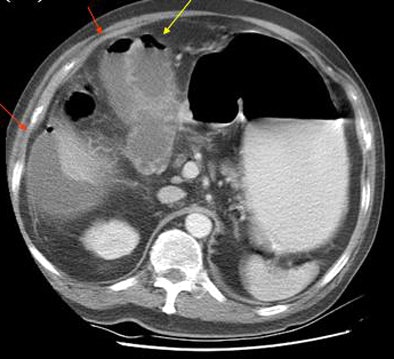

"Gallbladder rupture was seen in 16 of the 75, or about 21% of the cases," Chen said. "The most common CT findings included pericholecystic fat stranding in 71 of 75 patients, gallbladder wall enhancement, gallbladder wall thickening, and pericholecystic fluid collection."

In the analysis of CT images, "only seven findings showed significant differences between the rupture and the nonrupture group," he said. These included gallbladder wall defect (p = 0.000), intramural gas from the gallbladder (p = 0.043), intraluminal membrane of the gallbladder (p = 0.043), intraluminal gas of the gallbladder (p = 0.001), pericholecystic biloma or abscess (p = 0.009), free air (p = 0.001), and ascites (p = 0.019).

Multivariate analysis with logistic regression showed a significant association with gallbladder rupture in two findings: gallbladder wall defect (p = 0.0003, odds ratio: 30.18) and ascites (p = 0.049, odds ratio: 4.303).